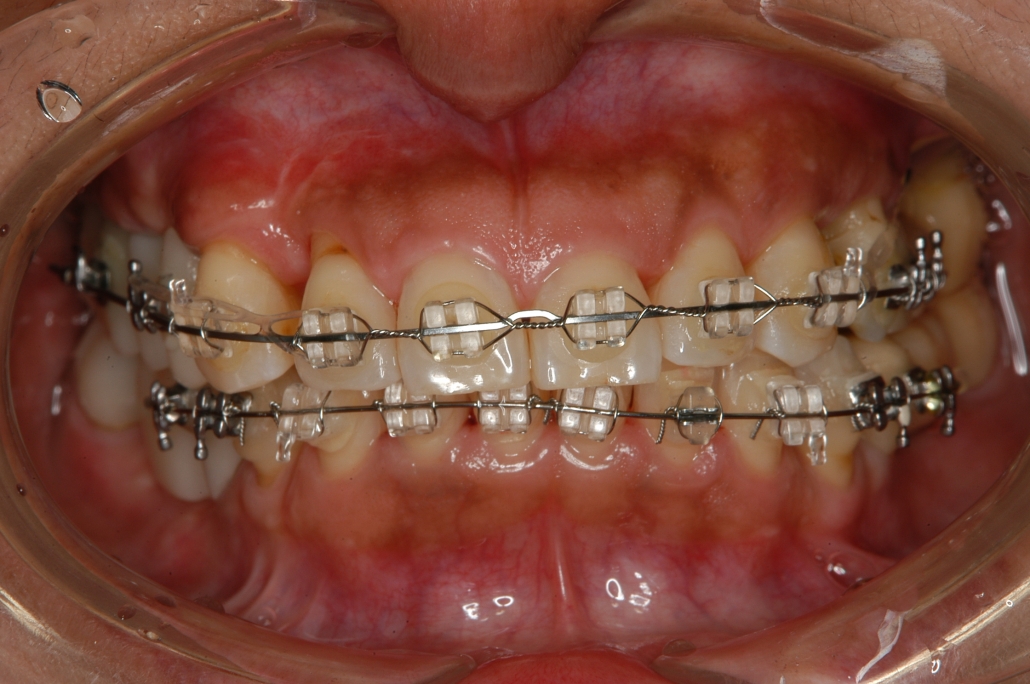

少回数ですむ悪い歯並び治療写真 ザ ホワイトデンタルクリニック

少回数ですむ悪い歯並び治療写真 ザ ホワイトデンタルクリニック

少回数ですむ悪い歯並び治療写真 ザ ホワイトデンタルクリニック